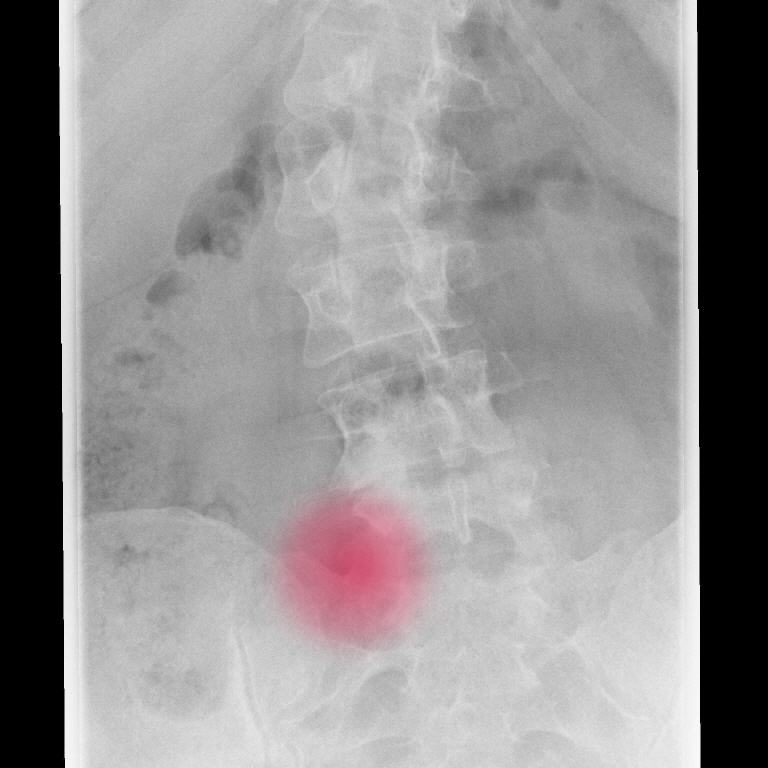

Leiden Sie unter akuten oder chronischen Rückenschmerzen? Die CT-gesteuerte Schmerztherapie (Selbstzahlerleistung) bietet eine zielgenaue und effektive Möglichkeit, aktivierte Gelenkarthrosen oder gereizte Nerven gezielt zu behandeln. Mithilfe der modernen CT-Bildgebung können Schmerzmittel und Cortison präzise an die betroffenen Stellen injiziert werden, wodurch eine schnelle und langanhaltende Linderung der Schmerzen erreicht wird. Unsere Schmerztherapien umfassen Facettenblockaden, ISG-Blockaden und periradikuläre Therapien (PRTs).

Für die zielgenaue Therapie benötigen wir zur Planung ein aktuelles MRT der LWS mit Kontrastmittel. Erst nach Sichtung der Bilder wird in einem Gespräch mit dem Patienten die genaue Anzahl der zu behandelnden Höhen festgelegt und somit dann auch erst die entgültigen Kosten berechnet.